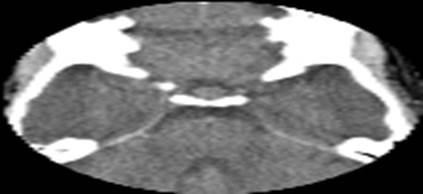

- Tomografía axial computarizada (TAC) de cráneo (simple) que se realizó el 19 de septiembre de 2008 2008.09.19: Macroadenoma hipofisiario (Figura 1).